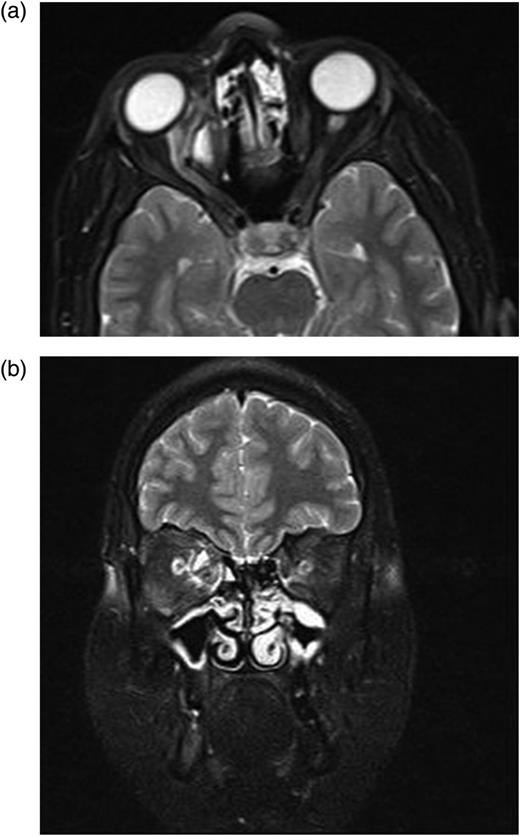

After second operation, in the first postoperative month, her ocular motilities were not restricted. Visual acuity was maintained at the same level (1/10). Control MR revealed no cystic structure except granulation tissue (Fig. 5a and b).

(a and b) After second operation, Control MRI in the first postoperative month shows granulation tissue.